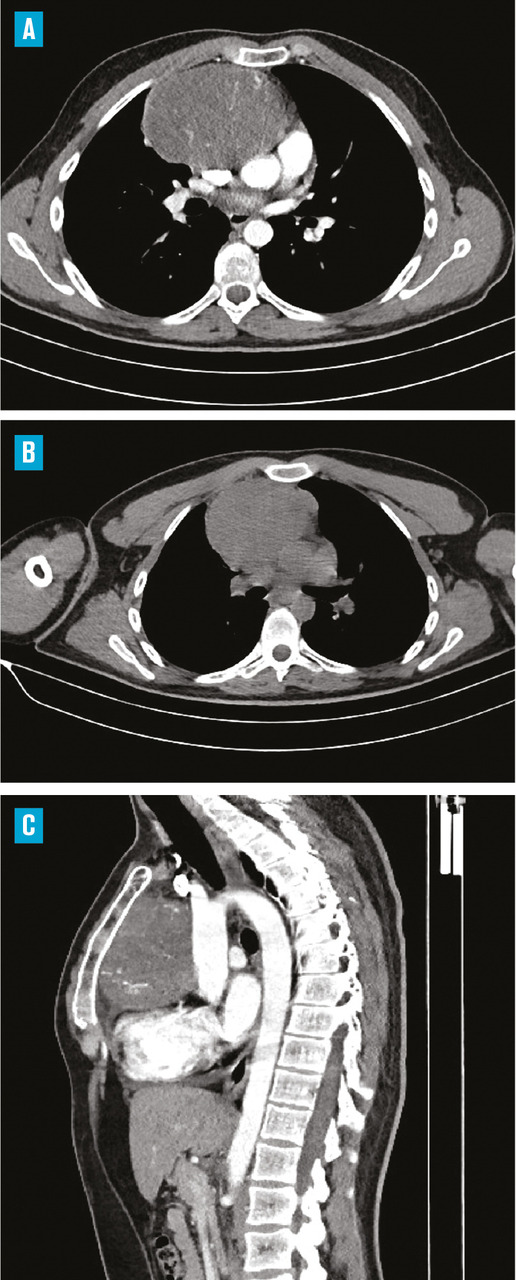

Le bilan biologique n’a pas montré de syndrome inflammatoire (hémogramme, protéine C réactive [CRP] et vitesse de sédimentation [VS] normaux). Les radiographies standard du bassin et du rachis lombaire, de même que l’échographie des hanches, étaient sans particularité. Mais la radiographie pulmonaire de face a mis en évidence une opacité médiastinale parahilaire droite se raccordant en pente douce avec le médiastin ainsi qu’une interface nette avec le poumon, évoquant une tumeur médiastinale (fig. 1).

Un complément scanographique a montré la présence d’une masse du médiastin antérosupérieur, de forme ovalaire, mesurant 10 × 9,5 cm, de contours réguliers et nets, et se réhaussant de manière hétérogène après injection du produit de contraste. Une adénopathie médiastinale y était associée avec la même densité, sans autre anomalie pleuropulmonaire (fig. 2).